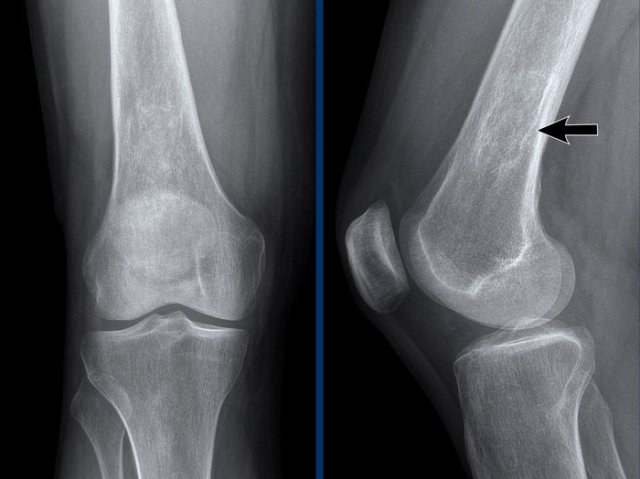

Chondrocalcinosis in CPPD

There are faint calcifications of the cartilage and meniscus both on the right side (white arrow) as well as on the left side (black arrows).

These can be caused by CPPD, but may be seen in other conditions as well, such as gout or osteoarthritis.

Also note the joint space narrowing and mild osteophyte formation.

CPPD has many features similar to osteoarthritis.

Knee osteoarthritis

Moderate to severe asymmetric narrowing of the medial compartment of the femorotibial joint space with osteophyte formation and subchondral sclerosis (Kellgren-Lawrence classification grade 3-4).